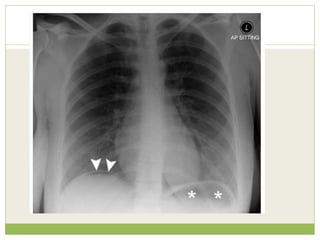

Clinical information provided ๏‚—Recent increase in shortness of breath ๏‚— No fever or productive cough ๏‚— Left shoulder and arm pain ๏‚— Heavy smoker ๏‚— Weight loss

Findings Left apical shadowing Raisedleft hemidiaphragm Increased extra-thoracic soft tissue density (*) with displacement of the scapula on the left (arrowheads) - compare with right

๏‚— Interpretation inview of clinical details ๏‚— Cancer - Smoker with weight loss and left apical consolidation/mass and no clinical features of infection ๏‚— Phrenic nerve palsy - Increased shortness of breath and raised left hemidiaphragm ๏‚— Brachial plexopathy - Arm pain and axillary soft tissue swelling

• #66ย Acute intra-alveolar pulmonary oedema with a bat's wing distribution.